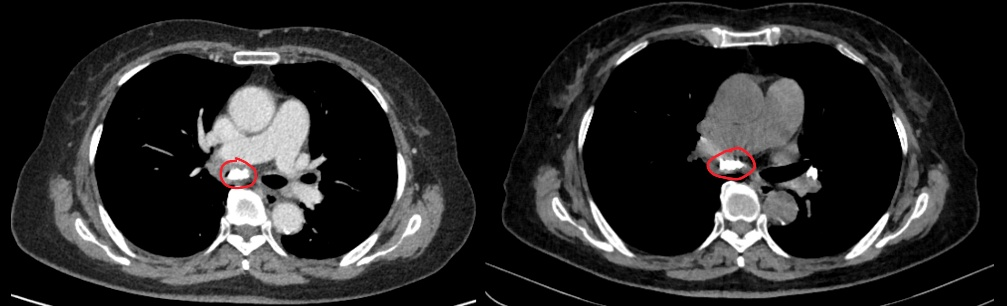

这一次,周阿姨的症状比以往更严重。除了熟悉的顽固性咳嗽、咳痰,还多了个新麻烦——“气短,尤其是一活动,气就不够用,胸口发闷”。胸部CT检查率先给出“异常信号”:周阿姨的纵隔内布满大量钙化灶,更危险的是,这些钙化灶已延伸到支气管内,几乎将右肺中间段完全堵塞,还引发了肺不张。结合症状与影像,医疗团队初步判断,周阿姨患的可能不是“老慢支”,而是罕见的“支气管结石”。

(CT所示右肺中间段支气管管腔狭窄被结石几乎完全堵塞)

随后的支气管镜检查证实了这个猜想。镜头下,一颗坚硬的“石头”牢牢卡在周阿姨的气道里,将右肺中间段堵得只剩一丝缝隙,这正是导致她9年间咳嗽难愈、近期气短的根源。